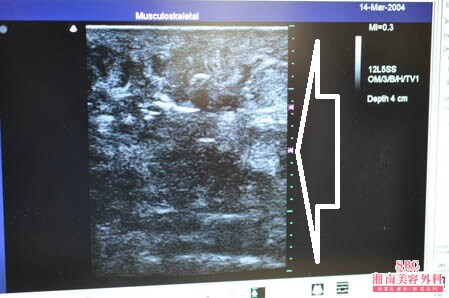

No.175973【脂肪吸引】湘南美容外科・全ドクターの脂肪吸引総括指導医であるあの有名な根こそぎ竹田先生の劇的ビフォーアフター!〜子供の頃に太っているのをいじめられた経験からコンプレックスになった太ももを細くする!右太もも後面術中3Dタッチビュー〜

いつものように3Dタッチビューから。